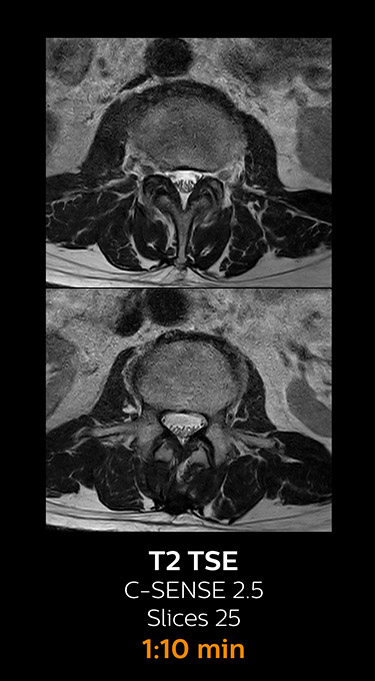

With Compressed SENSE, the scan time for the routine lumbar spine examination at KNC was reduced from 11:41 to 8:17 minutes,

MRI examination of the lumbar spine with Compressed SENSE

Ingenia 3.0T CX

Scan time 8:17 min. (was 11:41 min. without Compressed SENSE)